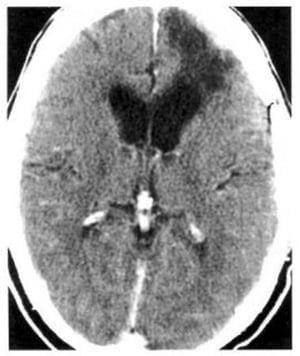

Hình 1.40. Nhồi máu não. Dưới 24 giờ, ảnh hưởng toàn bộ vùng chi phối của động mạch cảnh trong bên trái. Tổn thương mật độ thấp, giới hạn không rõ đẩy lệch não thất bên.